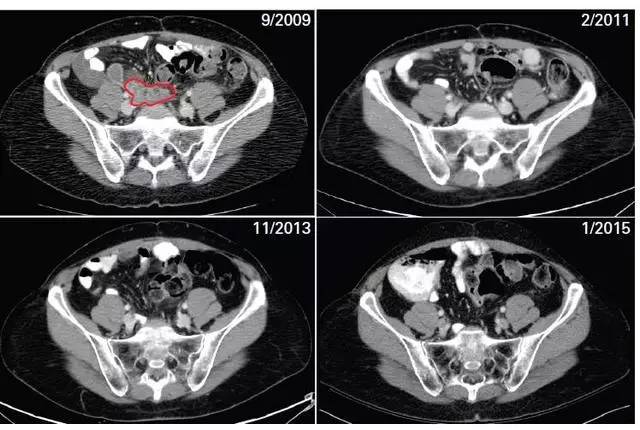

2009年9月服药前,肿瘤(图中标红的部分)还是好大一个;吃了药,肿瘤就开始慢慢消退,到2011年2月,已经基本找不着了;最近的一次复查(2015年元旦),毫无肿瘤复发的迹象!